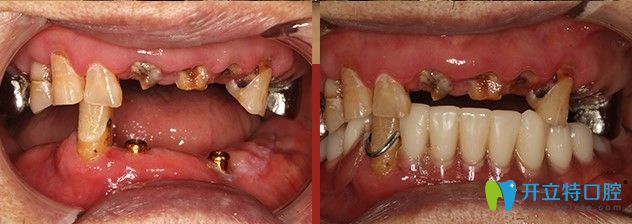

廣大口腔給韓重聲老人做種植牙的前后對(duì)比圖

顧客姓名:韓重聲/100歲

顧客身份:“解放戰(zhàn)爭(zhēng)、抗美援朝戰(zhàn)爭(zhēng)”功勛老軍人

顧客癥狀:上頜存牙較多,下頜僅剩五顆牙齒,四顆均有炎癥

治療方案:“高齡精準(zhǔn)種”,即刻負(fù)重

主治醫(yī)生:侯國(guó)鎮(zhèn)主任

下面我們一起來(lái)看看廣州廣大口腔給韓重聲老人做手術(shù)的過(guò)程吧!

一生辛勞,誰(shuí)都想安享晚年,老有口福。為種一口好牙,韓重聲老人早早來(lái)到了“高齡精準(zhǔn)種”發(fā)布會(huì)現(xiàn)場(chǎng)。發(fā)布會(huì)結(jié)束后,老人來(lái)到了精準(zhǔn)種植中心,韓老剛來(lái)到廣大口腔想要做種植的時(shí)候,口腔狀況并不樂(lè)觀。